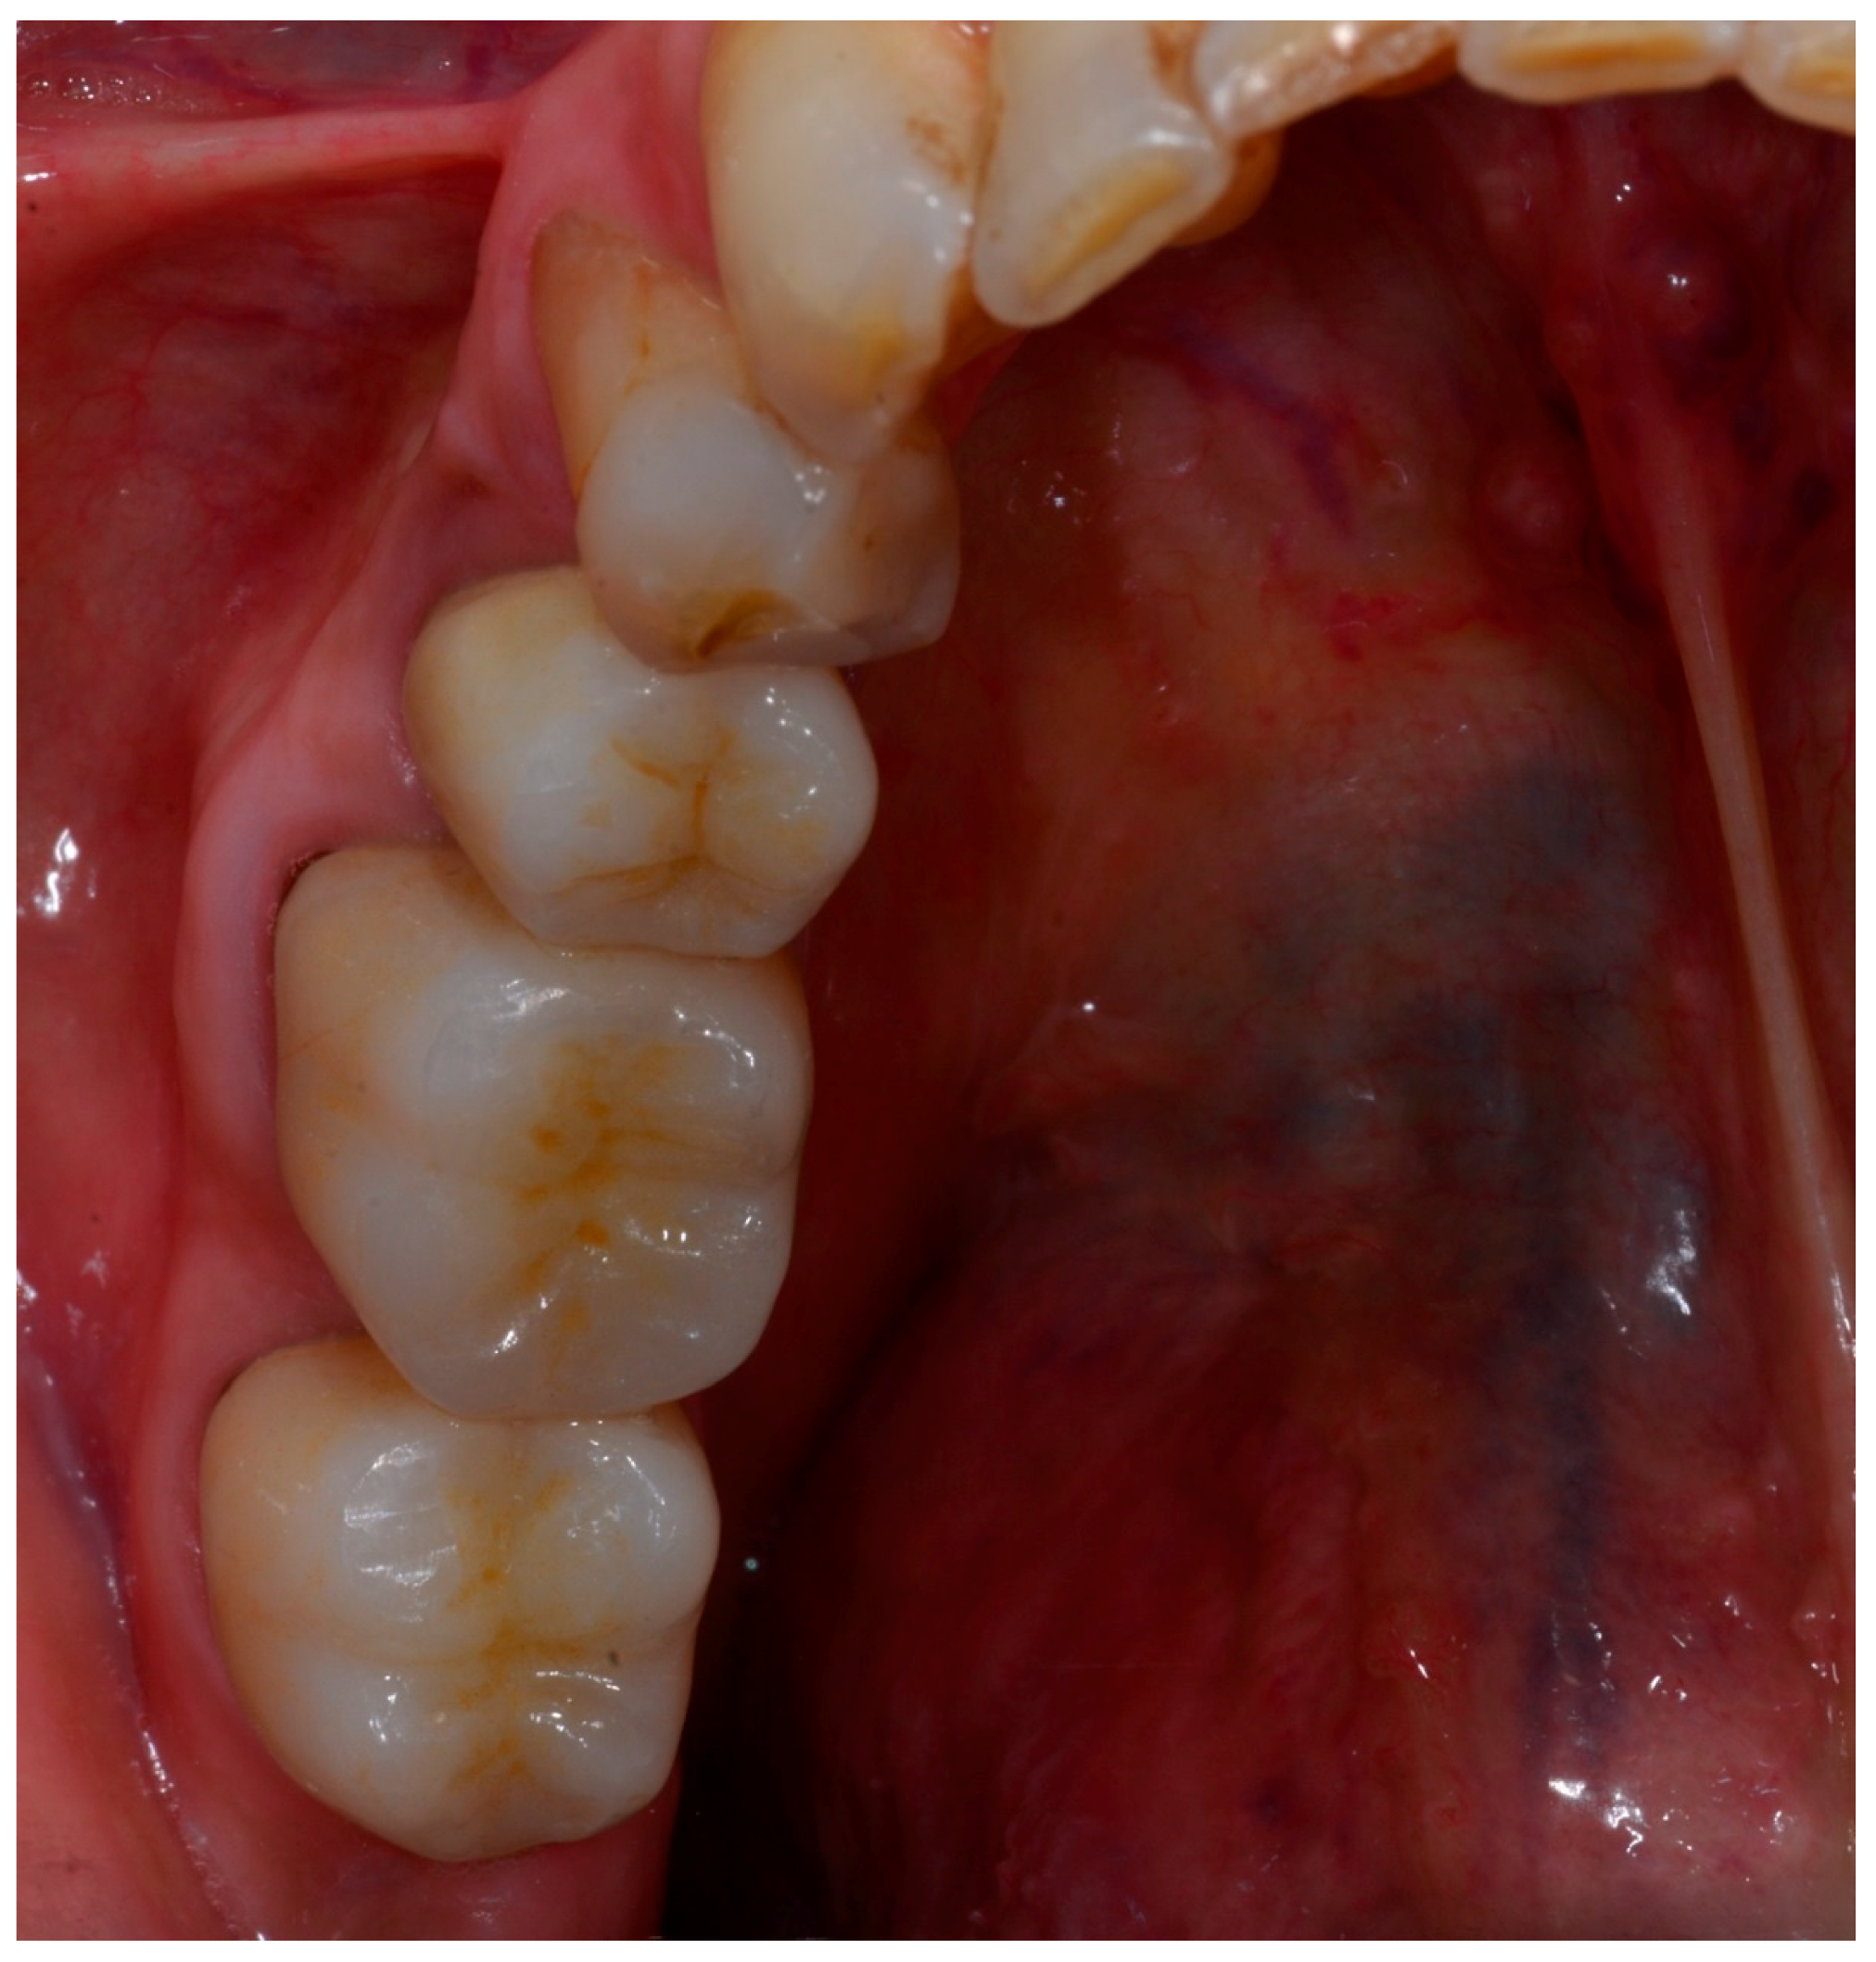

2. Materials and Methods